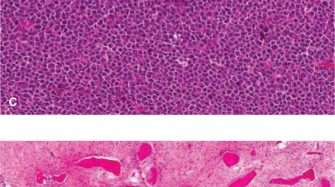

For Atypical Cartilaginous Tumors, a cortical window is created over the lesion. The window should be oval or rectangular with rounded corners to minimize stress risers. The window must be large enough to allow complete visualization of the tumor cavity.

Intralesional curettage is performed systematically. Hand curettes are used to remove the gross macroscopic tumor, which typically appears as glistening, bluish-white, avascular lobules of cartilage. Following gross removal, a high-speed mechanical burr is utilized to extend the curettage 1 to 2 millimeters into normal-appearing cancellous and cortical bone. This mechanical adjuvant is critical for removing microscopic tumor extensions within the trabecular bone.

Image

Chemical or physical adjuvants are subsequently applied to the cavity to induce necrosis of any remaining microscopic disease. Phenol (followed by alcohol neutralization), hydrogen peroxide, or liquid nitrogen (cryotherapy) are commonly employed. When using cryotherapy, careful protection of the surrounding soft tissues and neurovascular structures is imperative to prevent iatrogenic thermal injury. Multiple freeze-thaw cycles provide the maximum tumoricidal effect.